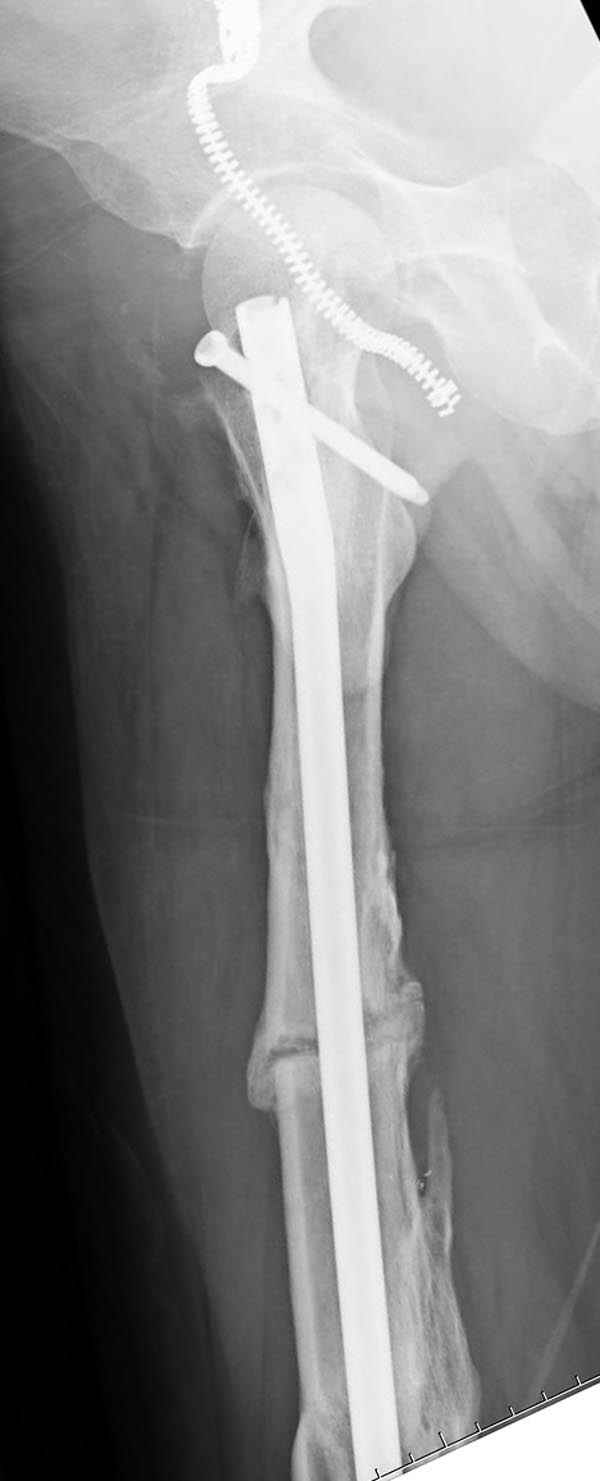

На следующий день произвели интрамедуллярный остеосинтез: этапы во время операции (рис №8, №9)

и последующих снимках (рис №10, 11, 12, 13) перелом сростается и передвигается с полной нагрузкой.